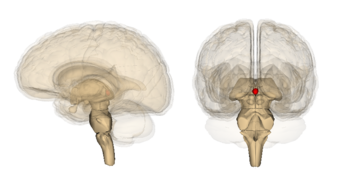

Pineal gland or epiphysis (in red) | |

غدة صنوبرية بالإنجليزية Pineal gland ، هي غدة صغيرة الحجم من الغدد الصماء تقع في المخ وهي المسؤولة عن إفراز هرمون الميلاتونين ولها علاقة بتنظيم معدل النمو الجسمي وكذلك عمليات النضج الجنسي في الكائن الحي.